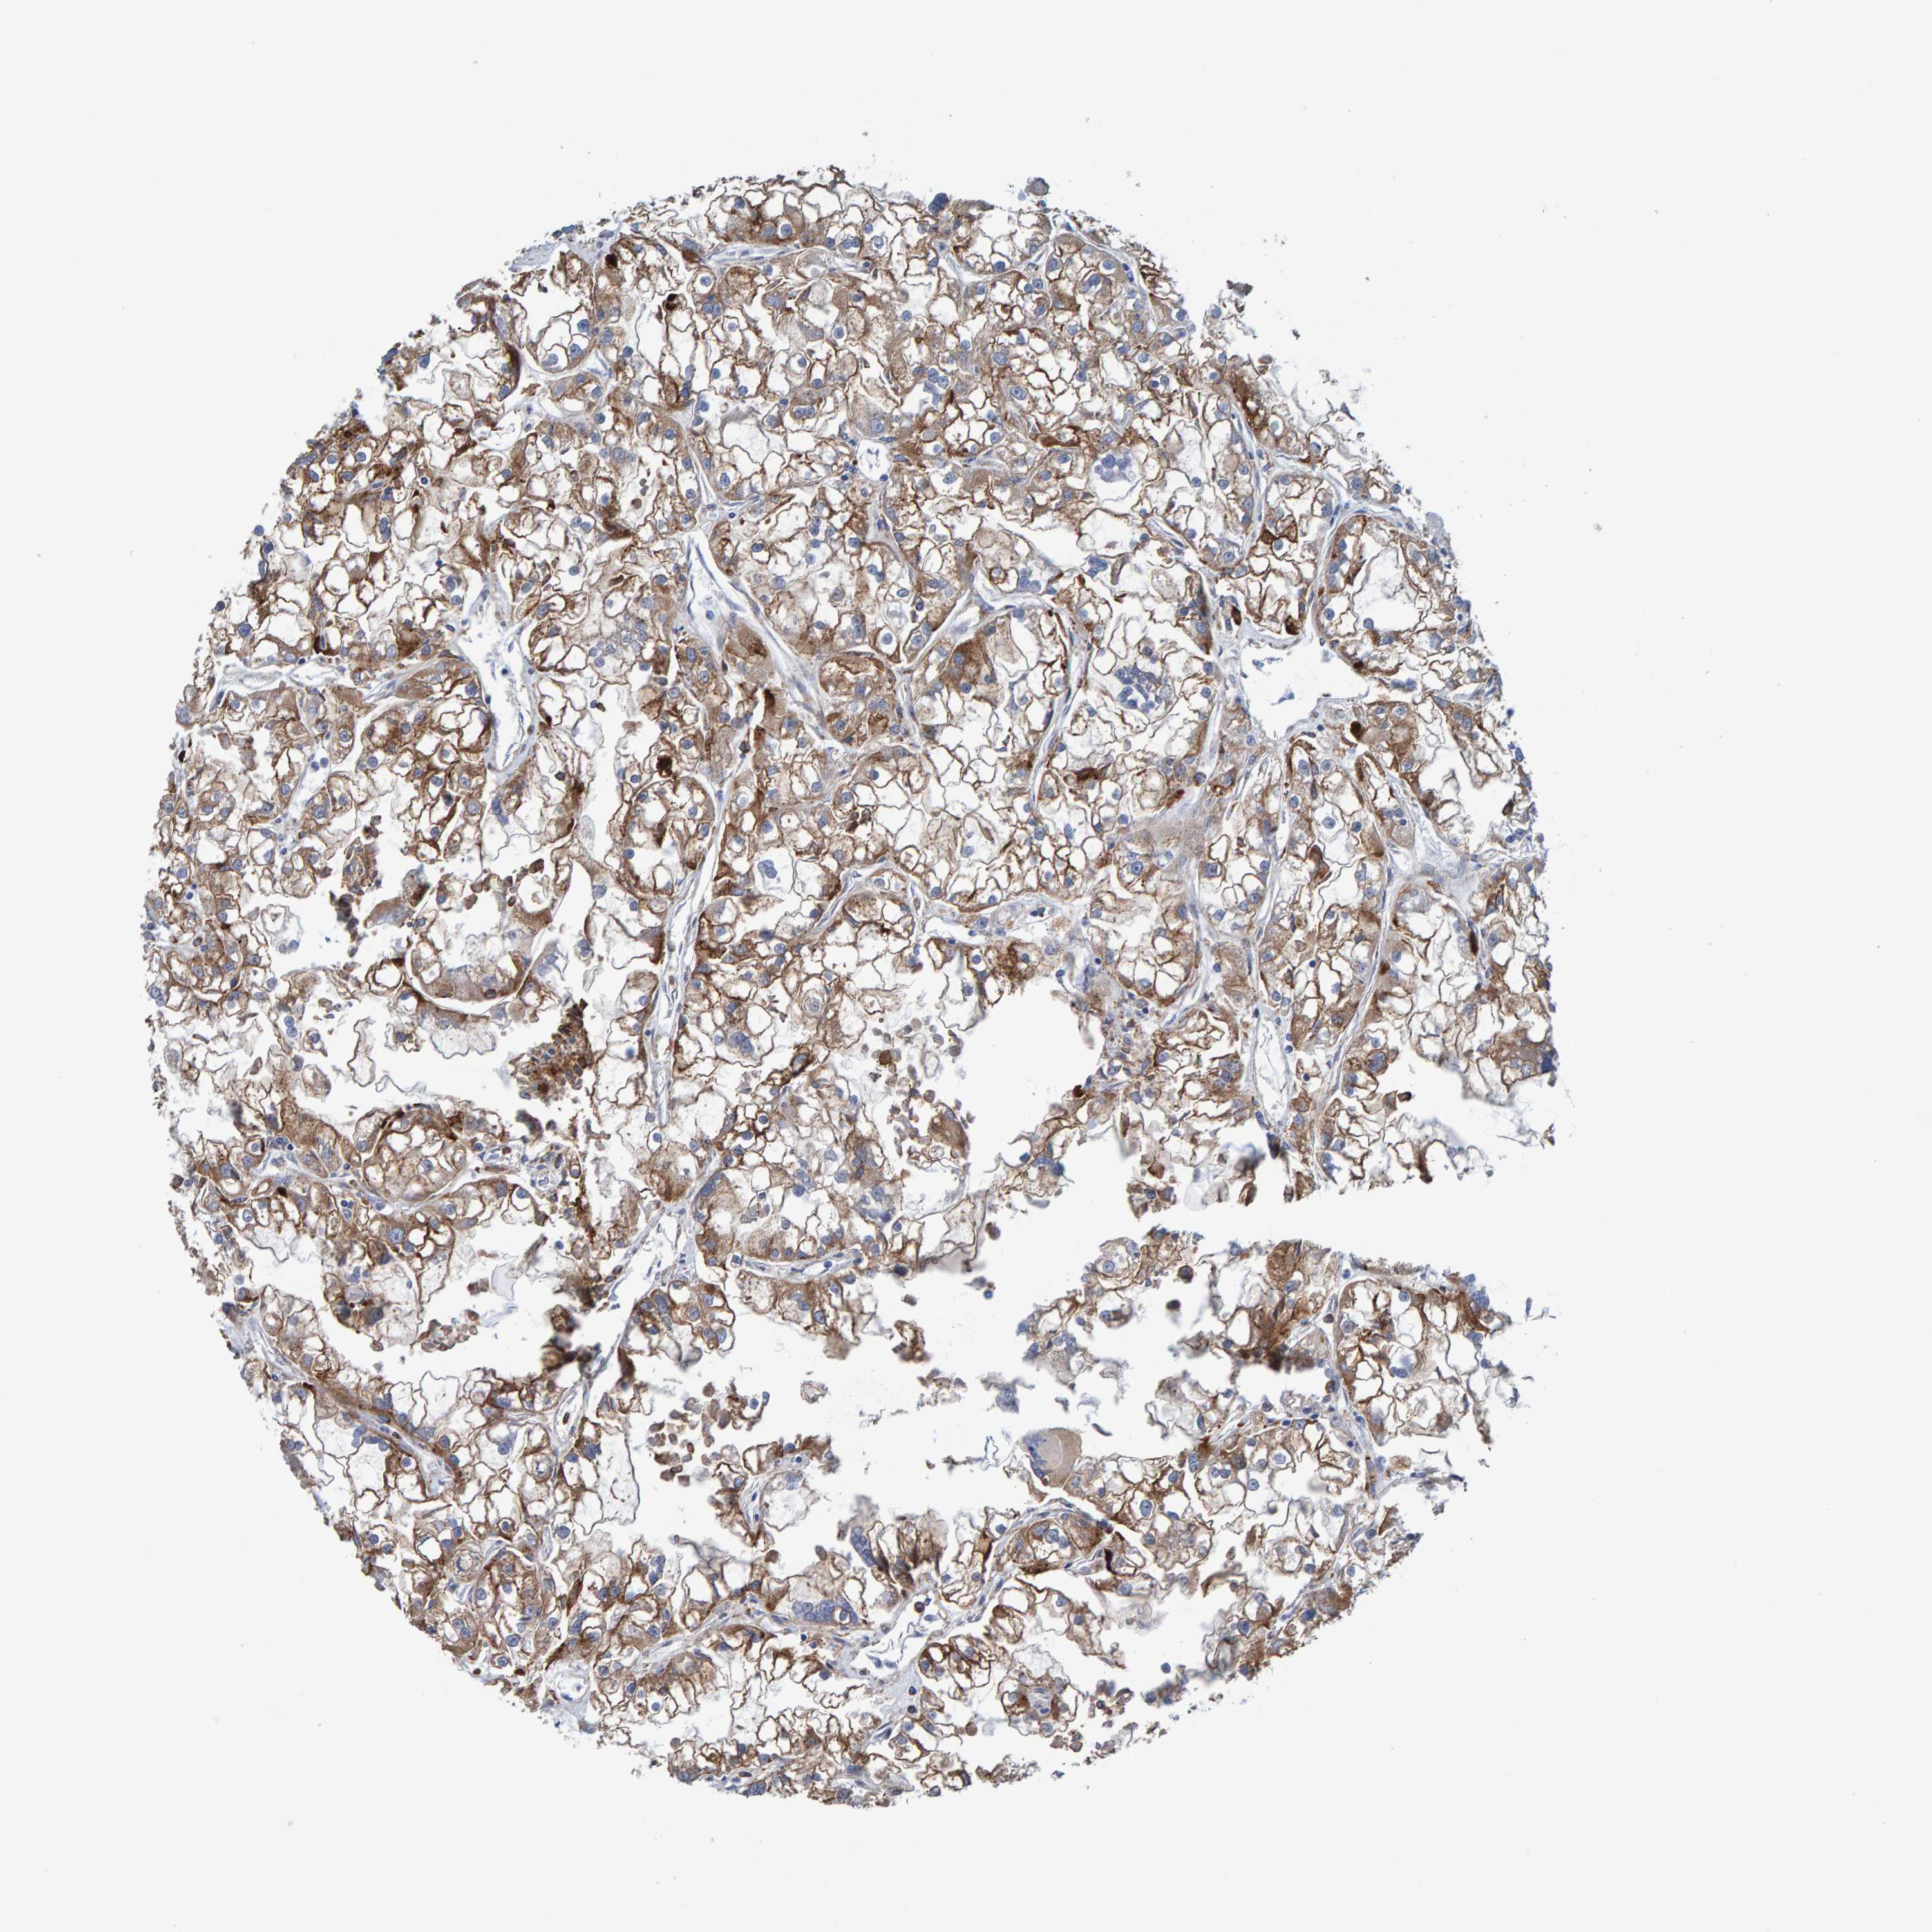

KIDNEY RENAL CLEAR CELL CARCINOMA (VALIDATION) - Interactive survival scatter ploti

The Survival Scatter plot shows the clinical status (i.e. dead or alive) for all individuals in the patient cohort, based on the same data that underlies the corresponding Kaplan-Meier plots. Patients that are alive at last time for follow-up are shown in blue and patients who have died during the study are shown in red.

The x-axis shows the expression levels (FPKM) of the investigated gene in the tumor tissue at the time of diagnosis. The y-axis shows the follow-up time after diagnosis (years). Both axes are complimented with kernel density curves demonstrating the data density over the axes. The top density plot shows the expression levels (FPKM) distribution among dead (red) and alive patients (blue). The right density plot shows the data density of the survived years of dead patients with high and low expression levels respectively, stratified using the cutoff indicated by the vertical dashed line through the Survival Scatter plot. This cutoff is automatically defined based on the FPKM cutoff that minimizes the p-score. The cutoff can be changed by dragging the vertical line or by entering a cutoff value in the square labeled "Current cut-off".

Under the Survival Scatter plot the p-score landscape (black curve; left axis) is shown together with dead median separation (red curve; right axis). Dead median separation is the difference in median mRNA expression between patients who have died with high and low expression, respectively. It is calculated as follows: median FPKM expression of dead patients with high expression - median FPKM expression of dead patients with low expression. This is intended to aid the user in visually exploring custom cutoffs and the associated p-scores and dead median separation.

Individual patient data is displayed and can be filtered by clicking on one or more of the category buttons on the top of the page. Categories describing expression level and patient information include: high, low, alive, dead, female, male and tumor stages. The scale of the x-axis can be toggled between linear and log-scale by clicking on the "x log" button. Mouse-over function shows TCGA ID, patient information and mRNA expression (FPKM) for each patient.

& Survival analysisi

Kaplan-Meier plots summarize results from analysis of correlation between mRNA expression level and patient survival. Patients were divided based on level of expression into one of the two groups "low" (under cut off) or "high" (over cut off). X-axis shows time for survival (years) and y-axis shows the probability of survival, where 1.0 corresponds to 100 percent.

LRP1 is not prognostic in Kidney Renal Clear Cell Carcinoma (validation)

Best expression cut offi

Based on the FPKM value of each gene, patients were classified into two groups and association between prognosis (survival) and gene expression (FPKM) was examined. The best expression cut-off refers the FPKM value that yields maximal difference with regard to survival between the two groups at the lowest log-rank P-value. Best expression cut-off was selected based on survival analysis .

When clicking on this number, the vertical dashed line indicating cut-off, the interactive survival plot, and the Kaplan-Meier curve will be adjusted to show results based on the best expression cut-off.

: 43.86

Median expressioni

Median expression refers to the median FPKM value calculated based on the gene expression (FPKM) data from all patients in this dataset. When clicking on this number, the vertical dashed line indicating cut-off, the interactive survival plot, and the Kaplan-Meier curve will be adjusted to show results based on the median expression.

: N/A

Median follow up timei

Median follow up time refers to the median time (years) after diagnosis with this type of cancer, based on clinical data from all patients in this dataset.

P scorei

Log-rank P value for Kaplan-Meier plot showing results from analysis of correlation between mRNA expression level and patient survival.

N/A

5-year survival highi

5-year survival for patients with higher expression than the expression cutoff.

For melanoma and glioma, 3-year survival is shown.

5-year survival lowi

5-year survival for patients with lower expression than the expression cutoff.

TCGA RNA samplesi

RNA-seq data is reported as average FPKM (number Fragments Per Kilobase of exon per Million reads), generated by the The Cancer Genome Atlas (TCGA) .

Normal distribution across the dataset is visualized with box plots, shown as median and 25th and 75th percentiles. Points are displayed as outliers if they are above or below 1.5 times the interquartile range. FPKM values of the individual samples are presented next to the box plot.

Average pTPM 32.0

Number of samples 100